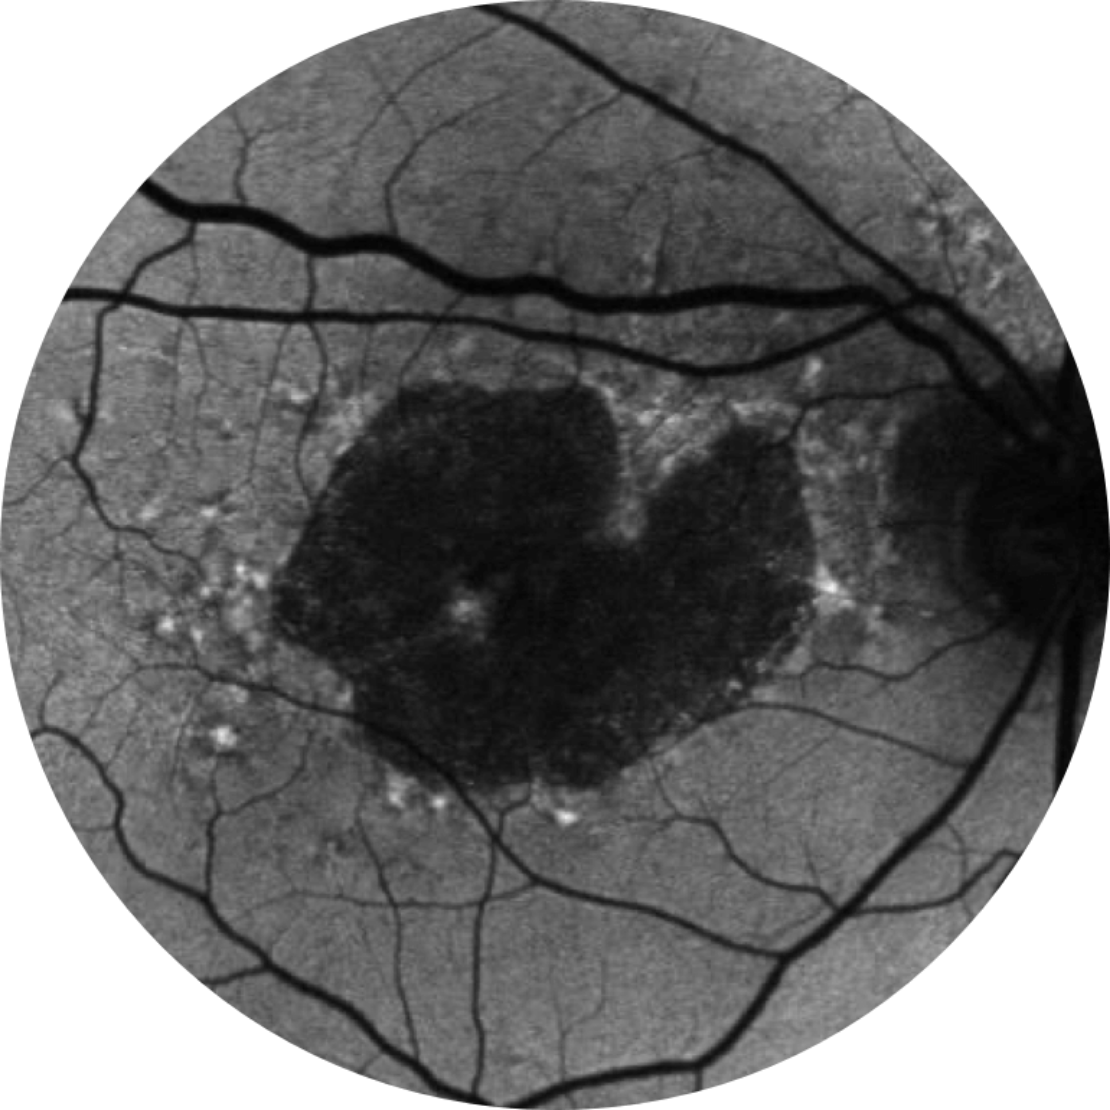

Autofluorescence du fond d’œil d’une rétine saine

L’angiographie par autofluorescence du fond de l’œil est actuellement une technologie d’imagerie standard permettant de visualiser l’épithélium pigmentaire rétinien (EPR) dans l’atrophie géographique.20

MAVC 20/63+, région AG 5,18 mm2

Référence Année 2

MAVC 20/80-2, région AG 10,39 mm2

Référence Année 5

MAVC 20/200, région AG 18,58 mm2

La croissance des lésions peut entraîner un déclin visuel.2,16,17

L’acuité visuelle n’est pas fortement corrélée à la croissance des lésions d’atrophie géographique. La vision fonctionnelle décline à mesure que les lésions grossissent.15

MAVC = meilleure acuité visuelle corrigée